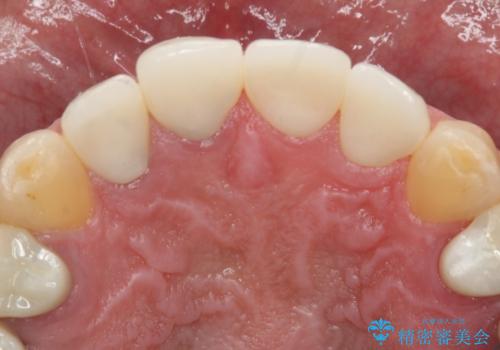

神経を取っている右上2番目の歯は根尖部に病巣があったため根管治療をした上で土台を立て、被せ物の作製を行いました。右上1番目の歯は他院にてとても大きく深い金属の土台が入れられており被せ物の色調に影響を与えていましたが、すべて取りきることのリスクが高いため途中まで除去し目立ちにくいファイバーコアで補強と色調の改善を行いました。